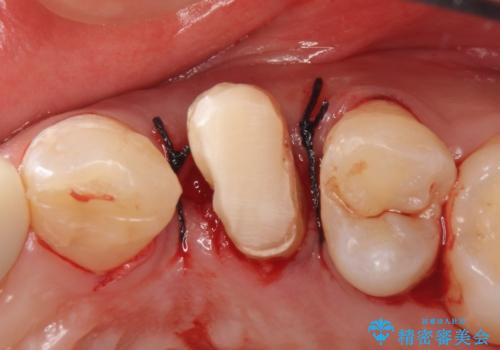

左上4の補綴物を除去したところ縁下歯質だったため、歯牙の挺出を提案し行いました。

挺出終了後は歯肉切除および骨外科により歯周組織を整え、オールセラミッククラウンによる補綴を行いました。